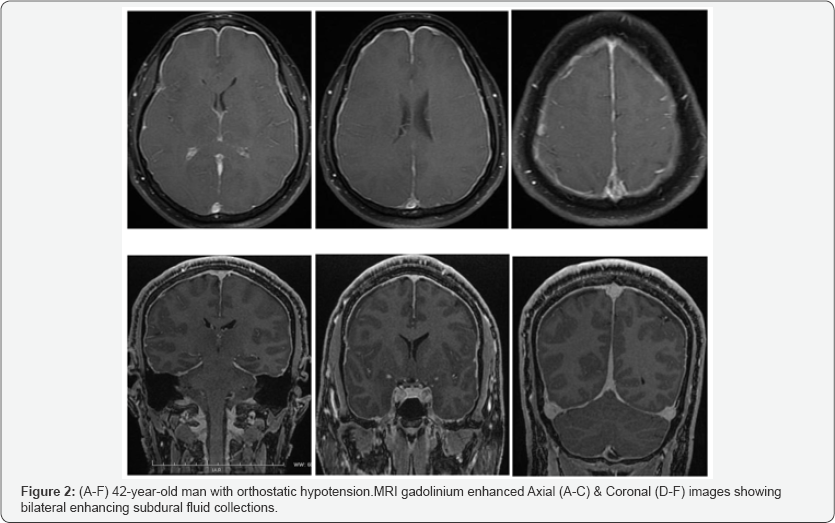

After contrast media injection, there was diffuse and uniform intense enhancement of all the dural surfaces, including the Falx and tentorium. The thickened and enhancing dura showed a smooth, non-nodular pattern (Figure 2A-2F). In addition, there was venous engorgement of the superior sagittal and transverse sinuses and prominent hyperaemic enhancement of the pituitary gland. The brain was sagging, with inferiorly displaced cerebellar tonsils and decreased pre-pontine CSF space (Figure 3A-3F).

Various imaging techniques help to diagnose SIH and guide treatment. MRI of the brain and spine identify signs of SIH. The common qualitative MRI findings in SIH represent the sum of loss of CSF volume and compensatory changes in response to the leakage. Thin, bilateral, subdural fluid accumulation over the cerebral and cerebellar convexities is commonly seen in about 50% of patients [20-22]. The pachymeningeal (dural) enhancement is bilateral, diffuse, involves both supratentorial and infratentorial compartments and spares the leptomeninges [7]. This common (in 80% of cases) and striking appearance has been likened to a “felt tip pen” outlining the thickened, enhancing dura in a diffuse and non-nodular pattern [23]. It is thought to be caused by engorgement of the small, thin-walled dilated blood vessels in the subdural zone [5].

Dural venous sinus engorgement [24,25] and Pituitary hyperaemia or enlargement [26] are also due to compensatory increase in the venous blood component to balance the loss in cranial volume and pressure, but are less constant and less striking signs of SIH. Increased height of the pituitary gland (mean ± SD, 6.9±2.3mm) has been reported to have a sensitivity of 63% and specificity of 97% for the diagnosis of intracranial hypotension [27].